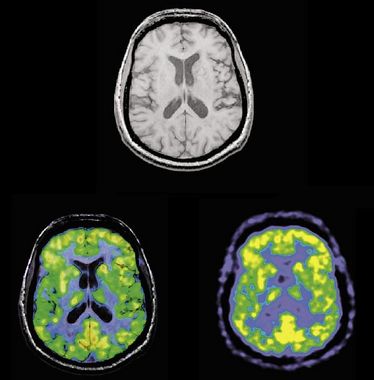

MR Aktuell 2015 (Fortbildung)

MR Aktuell 2015 (Fortbildung)